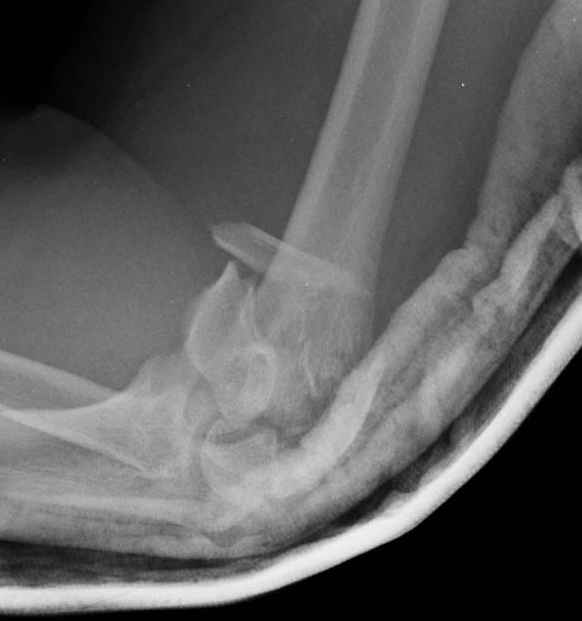

Женщина 42 лет, операция через неделю после перелома.

Д-з - открытый перелом мыщелков со смещзением и локтевой кости

без смещения - падение с лошади.

До операции снимки не очень, тем более в гипсе.

Остеосинтез закрытый (если так можно выразиться), т.е. без

разрезов. Длительность операции - около 1,5 часа со студентом.

6 щелчков ЭОПом.